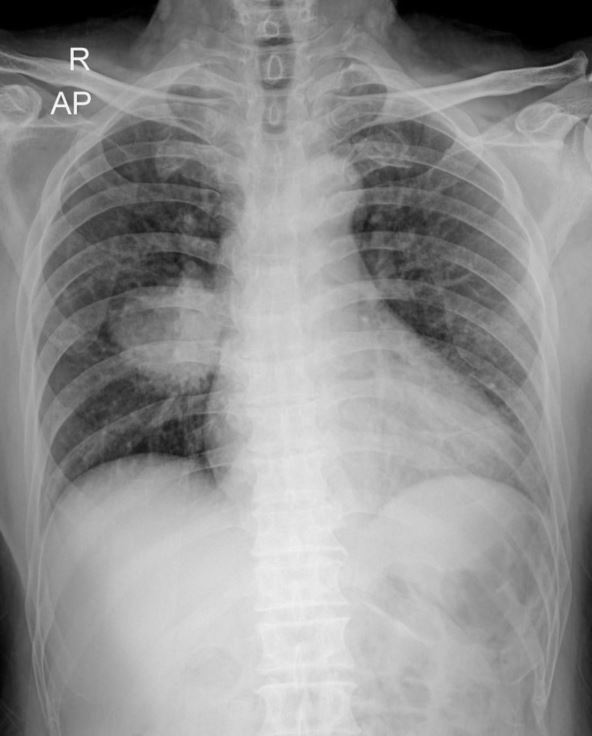

Rendgentski snimak

Foto: Shutterstock

Duvanski dim je kompleksna mešavina hemijskih supstanci: sadrži preko 7.000 komponenti, od kojih je najmanje 70 kancerogeno. Pored kancera pluća, duvanski dim dokazano izaziva još najmanje 16 vrsta kancera (usne duplje, grla, jednjaka, pankreasa i drugih organa).

Spisak se tu ne završava, lekari sugerišu da on utiče i napojavu: respiratornih bolesti (poput hroničnog bronhitisa i hronične opstruktivne bolesti pluća, kao i povećanog rizika od infekcija disajnih puteva), kardiovaskularnih bolesti (poput ateroskleroze, srčanog udara, povišenog krvnog pritiska), ali i povećanog rizika od moždanog udara.